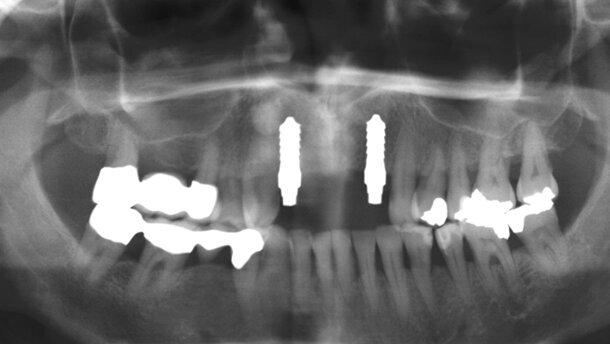

embedImagecenter("Imagecenter_1_139",139, "large");